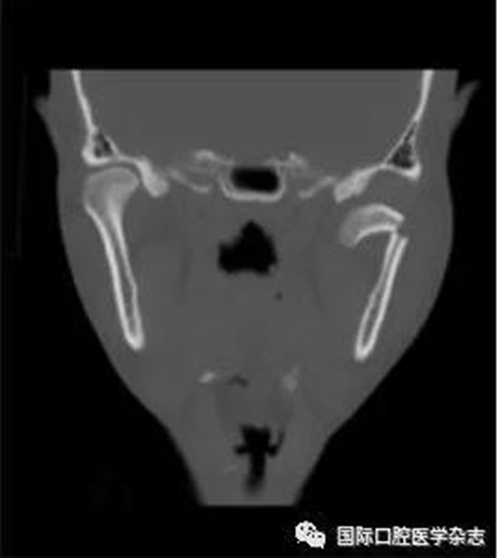

(4)關節(jié)強直(圖3):指因器質性病變導致長期開口困難或完全不能開口??煞譃殛P節(jié)內強直和關節(jié)外強直。關節(jié)內強直是由于一側或兩側關節(jié)內發(fā)生病變,造成關節(jié)內的纖維性或骨性粘連,也有人稱為真性關節(jié)強直。關節(jié)外強直是病變位于關節(jié)外上下頜間皮膚、黏膜或深層肌肉組織,形成頜間瘢痕攣縮(圖4),也有人稱為假性關節(jié)強直[7]。5)顳下頜關節(jié)感染:常由下頜關節(jié)附近化膿性病灶所致。多見于兒童中耳炎、腮腺炎等。此外還可由全身性傳染性疾病如麻疹、猩紅熱等引起。6)顳下頜關節(jié)外傷(圖5):外傷是引起開口受限的常見因素之一,最常見于下頜骨髁突骨折引起下頜運動受限[8]。

圖 4 頜間攣縮